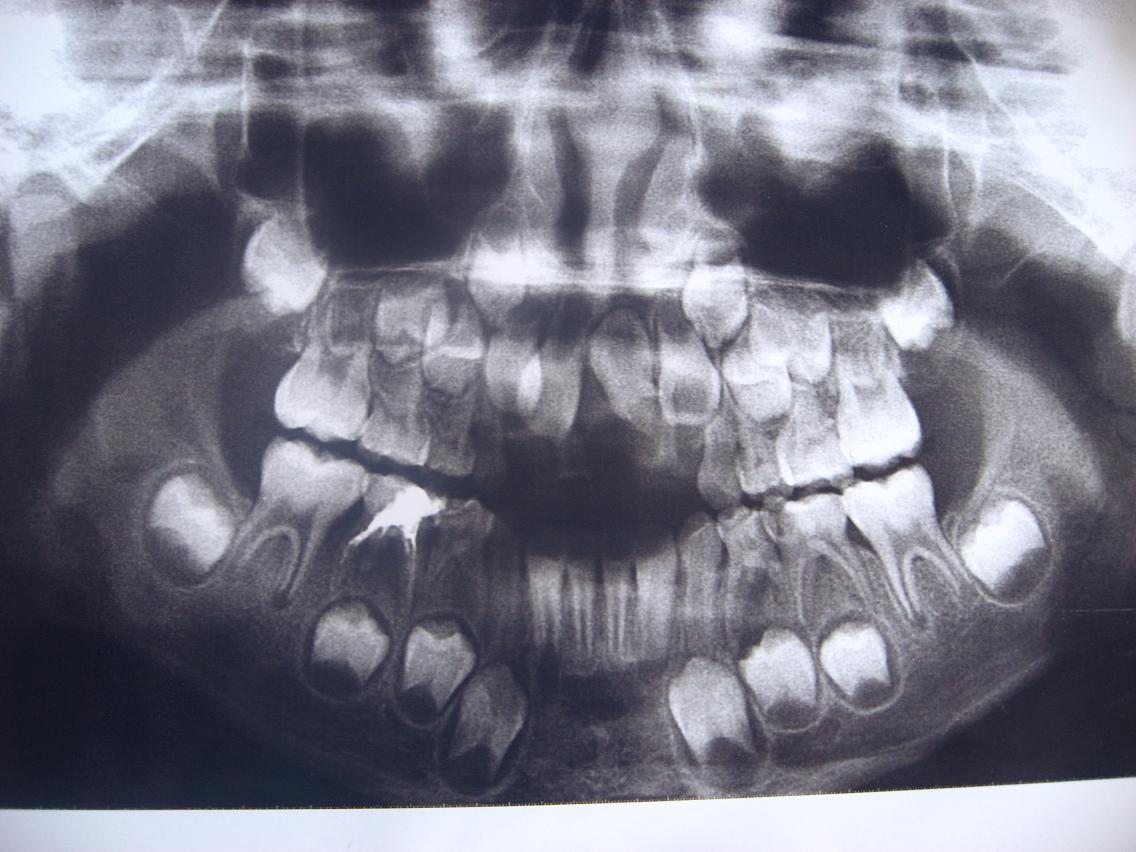

这个能看出乳牙还包裹着恒牙的小牙胚,经常给宝宝做牙齿检查非常重要。

不知宝宝看到这些扫描图会如何感想,一定会非常害怕看到自己的牙齿,要给宝宝养成每天刷牙、漱口的好习惯,抓好这次换牙的机会保护好牙齿。